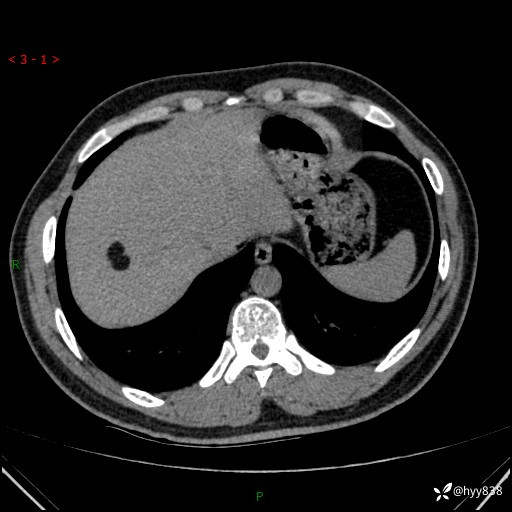

患者性别:男

患者年龄:28岁

简要病史:右肾肿瘤术后,常规复查

辅助检查:CT

临床诊断:右肾肿瘤术后

腹部CT+颅脑CT平扫